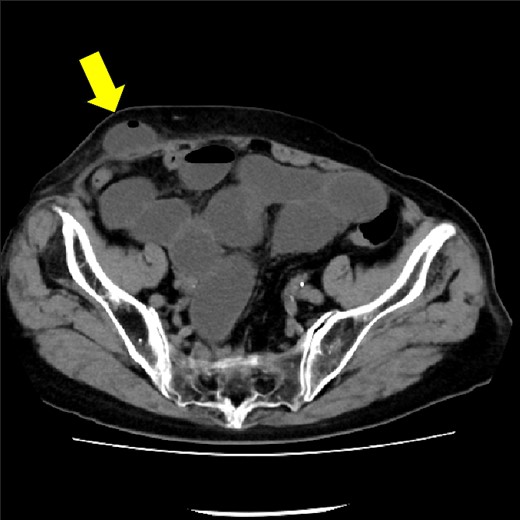

The drain was removed on postoperative day 2. On the night of the third postoperative day, the patient vomited. On the morning of the fourth postoperative day, mild abdominal pain and a ping-pong ball-sized bulge and induration were found near the surgical scar of the 5 mm port where the drain had been placed. CT confirmed an incarcerated small intestine and ileus in the 5 mm port scar where the drain had been placed (Fig. 2). Ileus removal was performed on the same day. First, the dilated wound for nephrectomy was opened, and the inside of the abdominal cavity was observed. A hanging small intestine was observed just below the 5 mm port (Fig. 3). Since it could not be conquered manually, a 2 cm vertical incision was made on the 5 mm port wound. The small intestine penetrated the anterior layer of the rectus abdominis muscle, so the fascia was carefully incised to avoid damaging the small intestine. The small intestine was returned to the abdominal cavity. The small intestine was slightly discolored (Fig. 4), but after discussion with the gastrointestinal surgeon, it was determined that it was not necrotic. No small intestine resection was performed. The wound was carefully closed using fascial sutures to prevent recurrence. The fascia was weak, likely because this patient was taking steroids. The ileus has not recurred since then. The pathological results indicated a maximum diameter of 30 mm, consistent with papillary renal cell carcinoma, classified as pT1a G3 > G2, with negative margins.